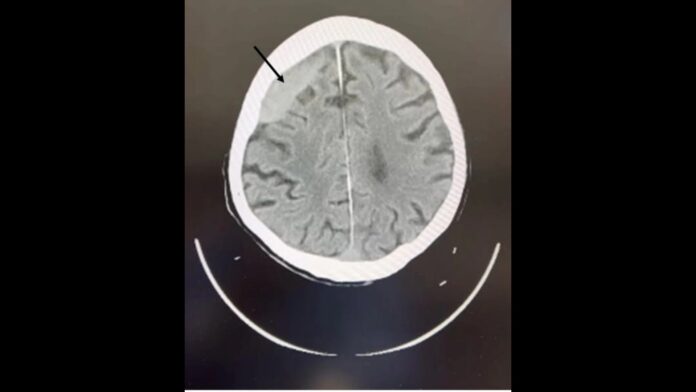

葉宗勳指出,老翁送醫時主訴頭暈、跌倒,後腦有外傷,電腦斷層掃描顯示右額葉出現一塊亞急性硬腦膜下血腫,並非剛跌倒造成的新傷,而是過去跌倒所致。這類血塊會隨時間慢慢擴大,壓迫腦組織導致神經功能異常,像是頭暈、癲癇,甚至昏迷、呼吸困難。